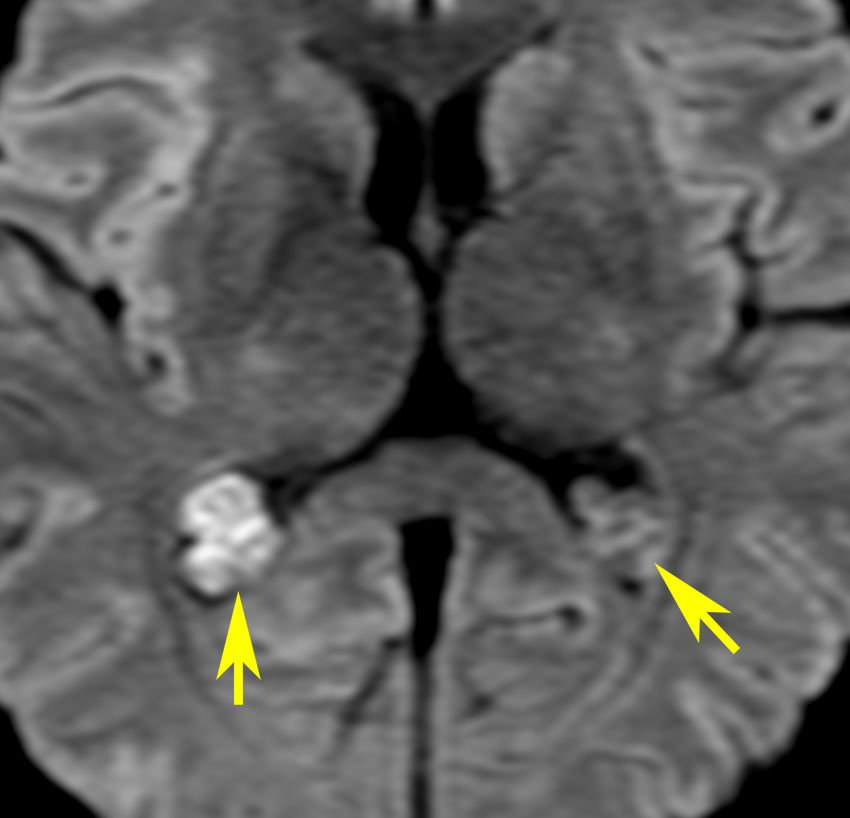

側脳室側頭角の脈絡叢乳頭腫です。黄色い矢印は腫瘍動脈で,前脈絡叢動脈といいます。ここを遮断すると出血が止められます。